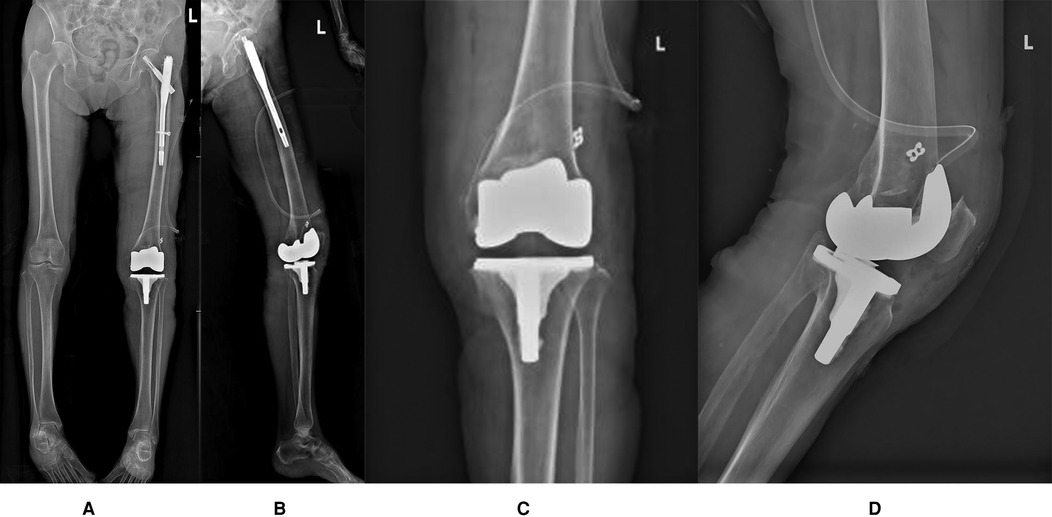

Clinical examination revealed a mild varus deformity of the left lower limb, with approximately 10° of varus alignment. Mild tenderness was noted over the medial patella. The active range of motion of the left knee joint was 0–110°, while passive range reached 0–120°. Patellar dislocation occurred when the knee is flexed at 40° (refer to Supplementary Video S1), with tolerable pain and a visual analogue scale (VAS) score of 5 (6), the knee society score (KSS) clinical score was 57, functional score was 15, and the Oxford Knee Score (OKS) was 41. When the joint is extended, the patella can be reduced; however, forced reduction impedes further knee flexion. The knee remained stable under varus and valgus stress, with negative anterior and posterior drawer tests at 90° of flexion. Full-length frontal radiograph of the lower limb and frontal radiograph of left knee joint demonstrated degenerative changes in both knees, including medial compartment narrowing and multiple osteophyte formation. Possible osteochondromas were noted at the medial upper tibial margins bilaterally, along with bilateral knee varus and patellar dislocation (refer to Figures 1AD). Computed tomography (CT) further validated the aforementioned diagnosis (refer to Figure 1E).

Figure 1

Figure1-Figure4 are preoperative iradiograph: degenerative changes in both knee joint, bilateral genu varum, possible osteochondroma on the medial border of the upper ends of both tibias, suspected patellar dislocation, and the right femur with intramedullary rod fixation. Figure5 revealed left patellar dislocation, is a CT scan series showing axial slices of the knee with anatomical landmarks labeled for alignment assessment.

Figure 1. (A) Full-length frontal radiograph of the lower limb; (B) Full-length lateral radiograph of the lower limb; (C) Frontal radiograph of left knee joint; (D) Lateral radiograph of left knee joint; (E) CT axial images of left knee joint. [The tibial tuberosity–trochlear groove (TT-TG) distance is 13.4 mm].